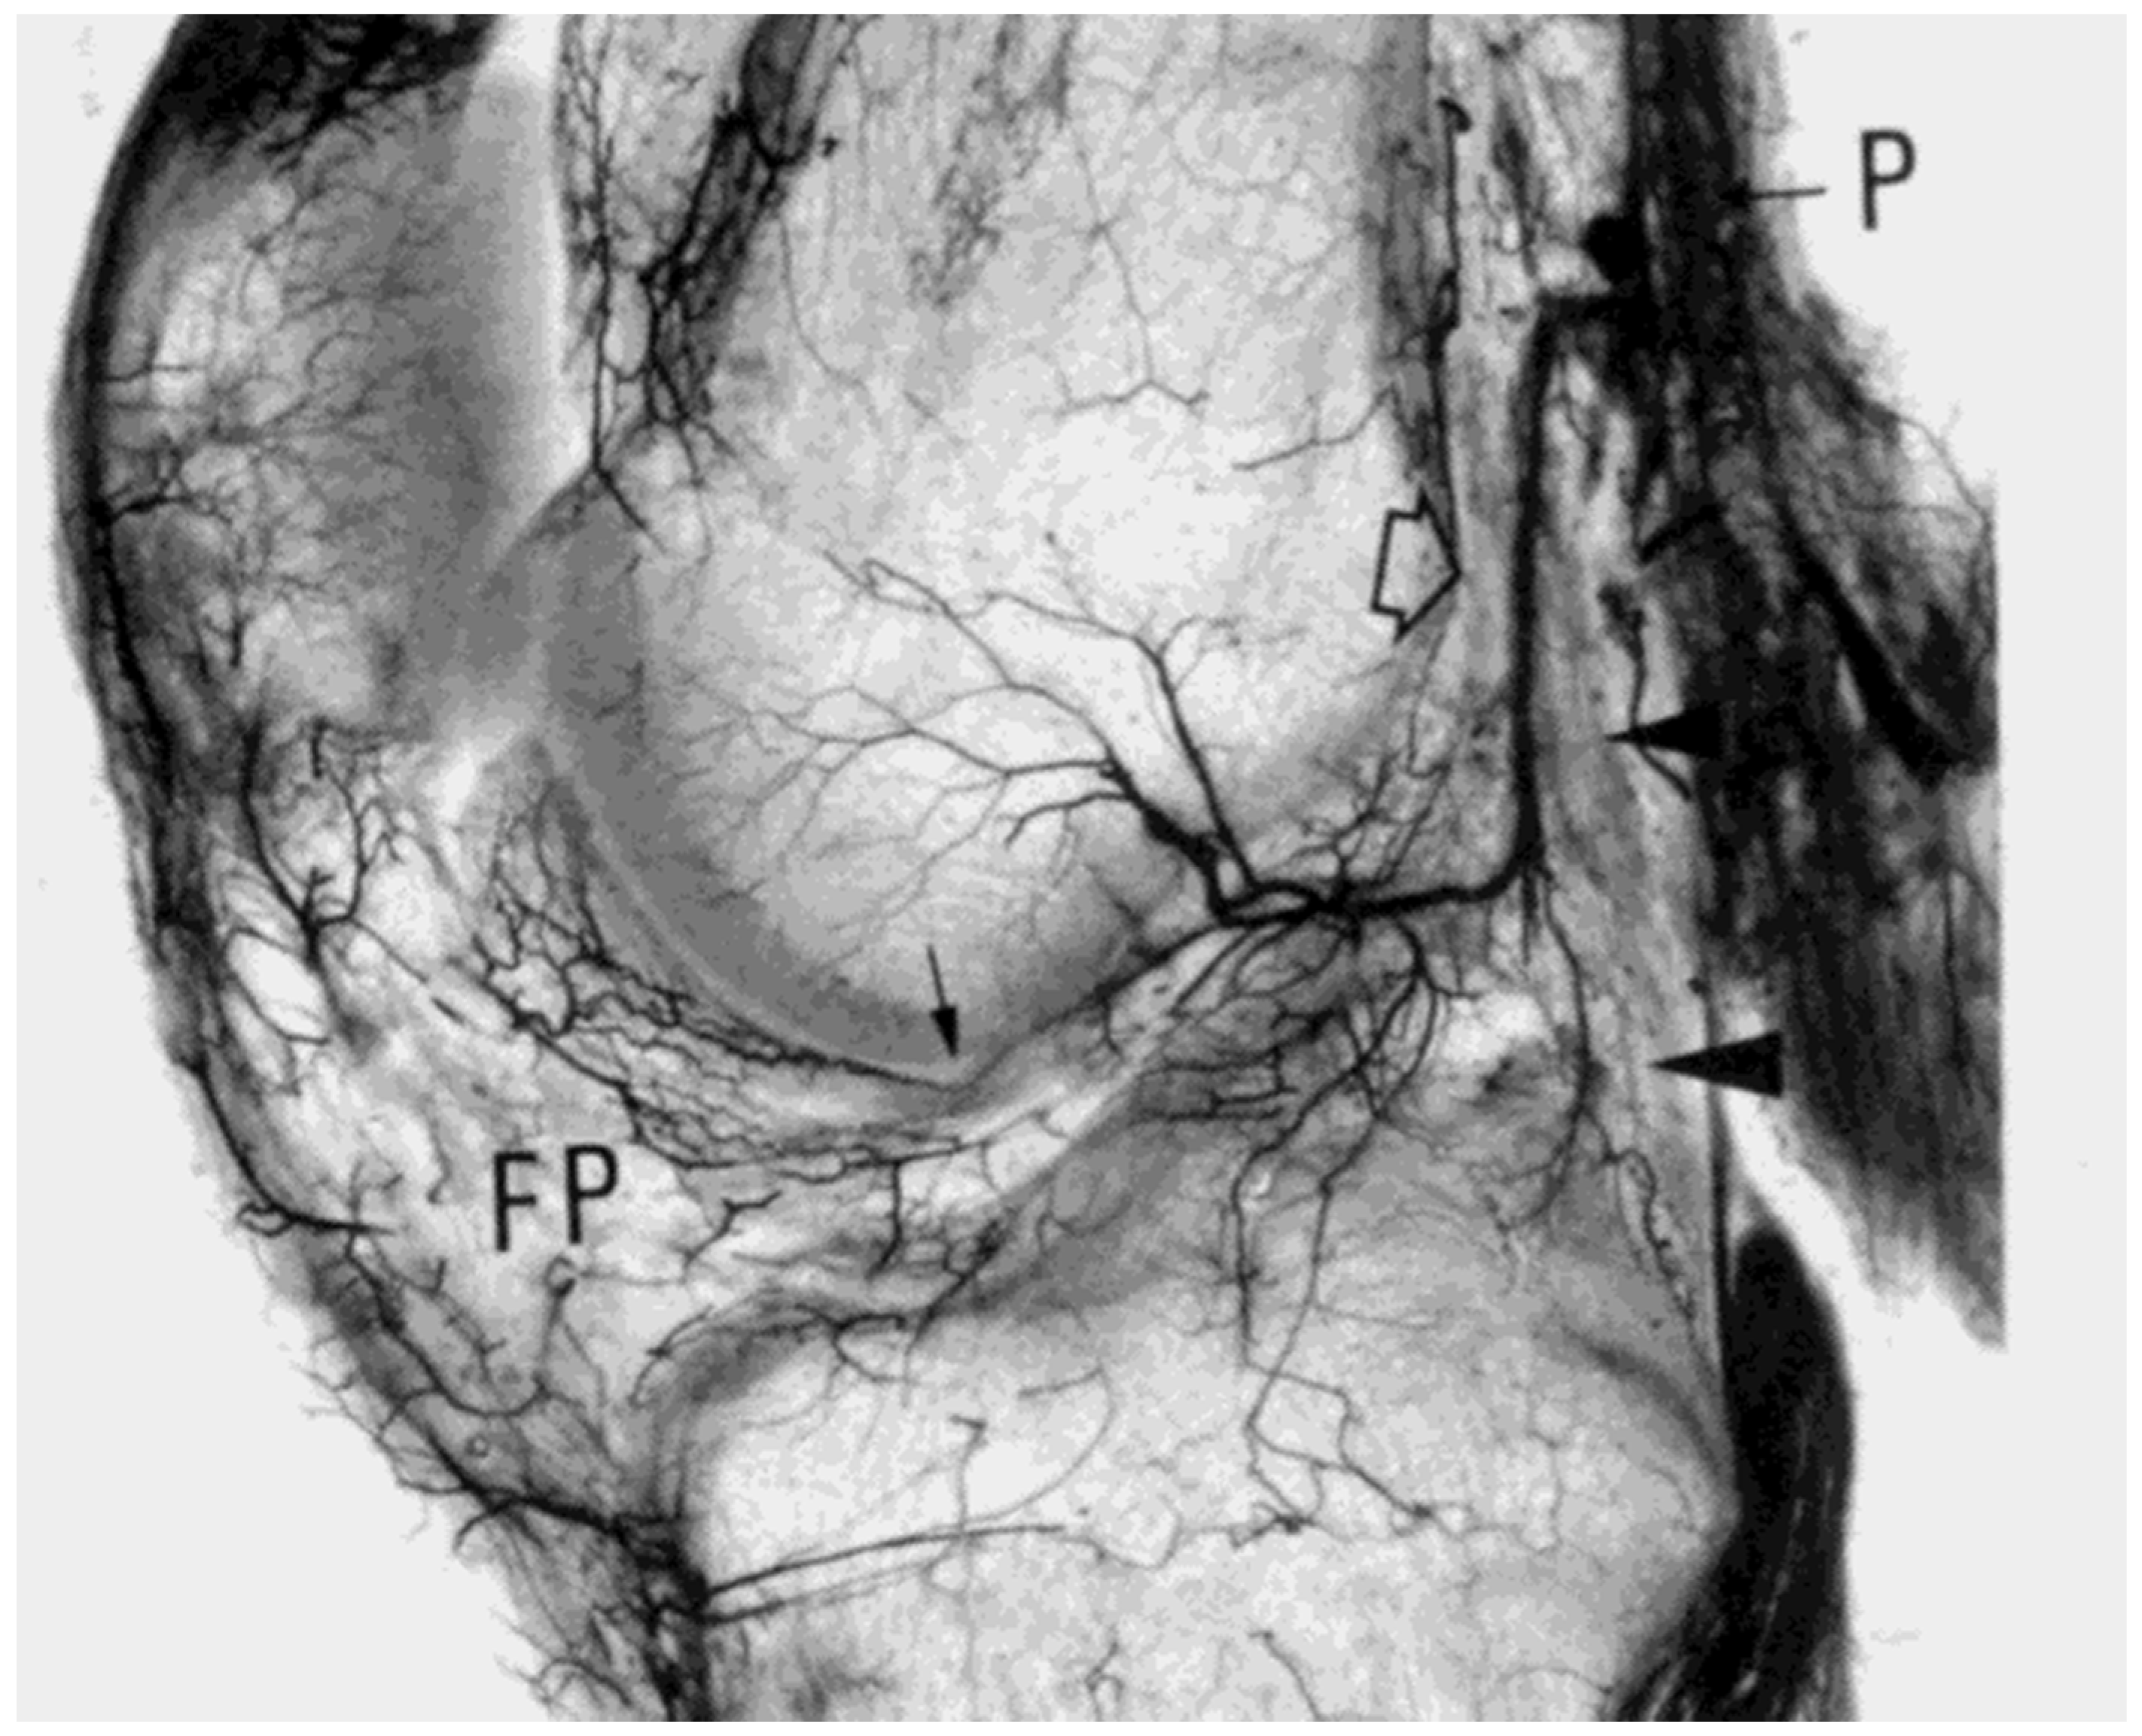

- Scapinelli, R. Vascular anatomy of the human cruciate ligaments and surrounding structures. Clin. Anat. 1997, 10, 151–162. [Google Scholar] [CrossRef]

- Petersen, W.; Hansen, U. Blood and lymph supply of the anterior cruciate ligament: Cadaver study by immunohistochemical and histochemical methods. J. Orthop. Sci. 1997, 2, 313–318. [Google Scholar] [CrossRef]

- Petersen, W.; Zantop, T. Anatomy of the anterior cruciate ligament with regard to its two bundles. Clin. Orthop. Relat. Res. 2006, 454, 35–47. [Google Scholar] [CrossRef] [PubMed]

- Duthon, V.B.; Barea, C.; Abrassart, S.; Fasel, J.H.; Fritschy, D.; Ménétrey, J. Anatomy of the anterior cruciate ligament. Knee Surg. Sports Traumatol. Arthrosc. 2006, 14, 204–213. [Google Scholar] [CrossRef]